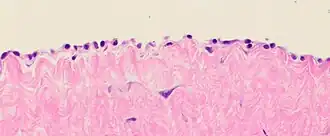

9. ^ Image by Mikael Häggström, MD. Sources for mentioned features:

- "Mesothelial cytopathology". Libre Pathology. Retrieved 2022-10-18.

- Shidham VB, Layfield LJ (2021). "Introduction to the second edition of 'Diagnostic Cytopathology of Serous Fluids' as CytoJournal Monograph (CMAS) in Open Access". CytoJournal. 18: 30. doi:10.25259/CMAS_02_01_2021. PMC 8813611. PMID 35126608.